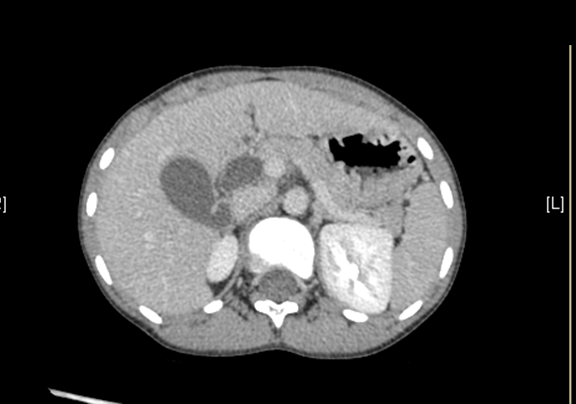

上腹部CT平扫:先天性胆管囊状扩张症并胆囊结石、胆囊炎症。

上腹部增强CT:肝总管-胆总管中上段梭形增宽,符合先天性胆管扩张所见(Ⅰ型)。

术前CT检查:

动脉期

静脉期

平衡期